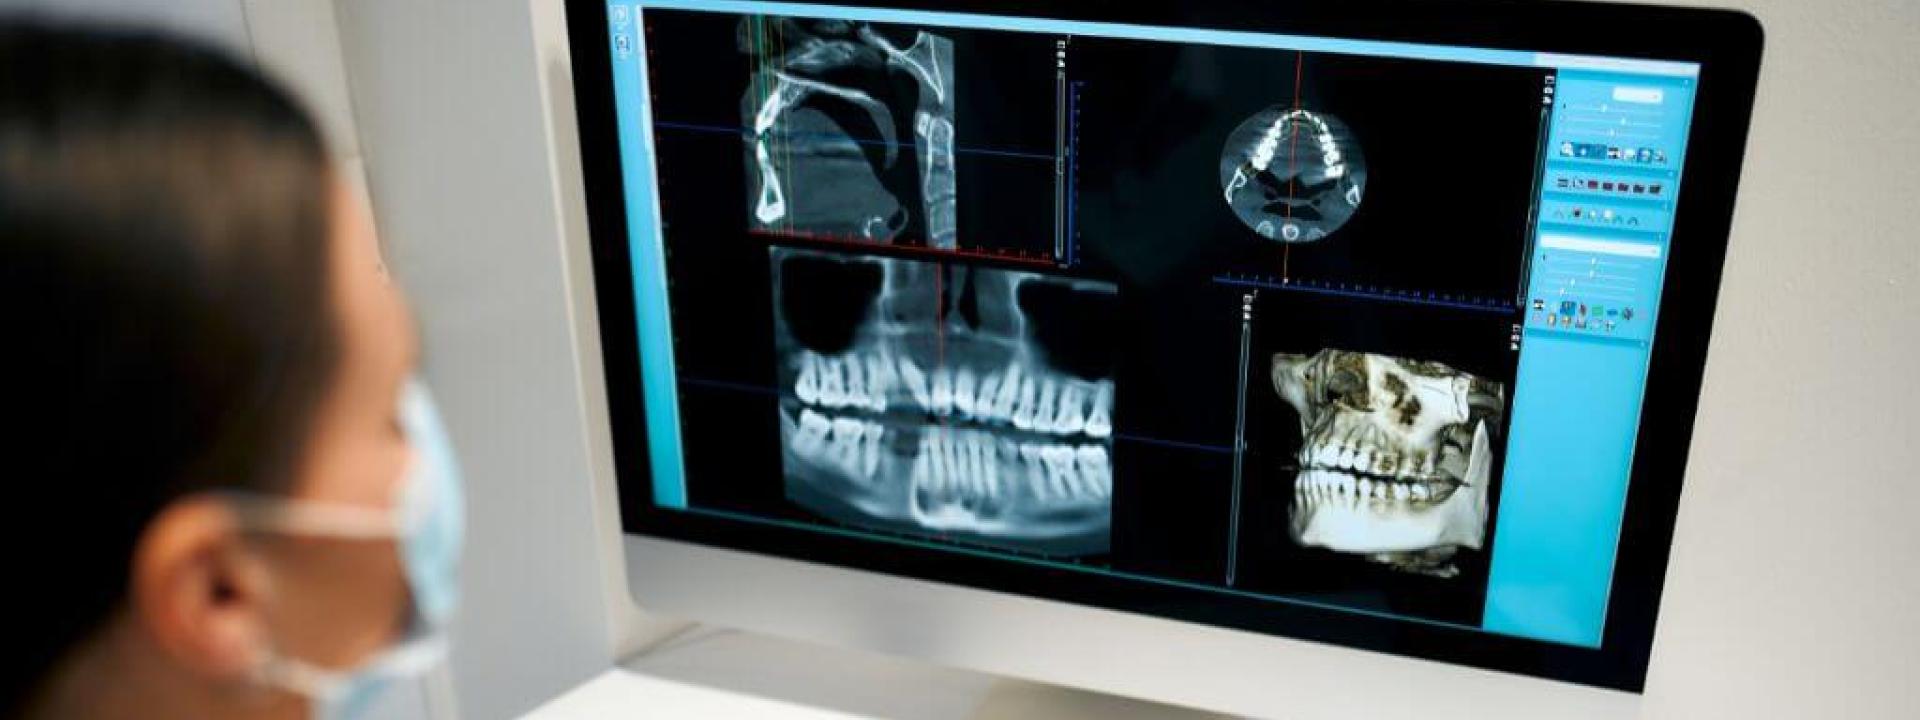

Imagine taking a 360-degree photo of your mouth — that’s essentially what a panoramic X-ray does. This type of X-ray captures your entire mouth, including all your teeth, both upper and lower jaws, and the surrounding structures, in a single image.

When having a panoramic X-ray done, you’ll stand still while a machine rotates around your head. It might sound high-tech (and it is!), but it’s quick, easy, and completely painless. These X-rays are incredibly useful for planning treatments like dentures, braces, or implants. They also help us spot impacted wisdom teeth, jaw disorders, and even some types of tumors.